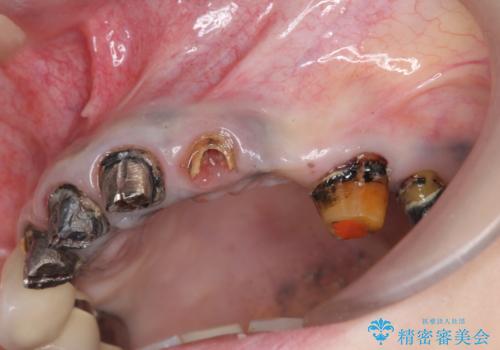

- 「歯がぐらぐらして噛めない。」、全体的な治療を希望されて来院されました。

クラウン・コアを除去したところ支台となる歯は破折し残すことが難しい状況でした。

抜去を行ったのち、インプラント治療を計画しますが骨量が少ないため、まず骨の造成を行ったのちインプラントを埋入していく治療計画としました。